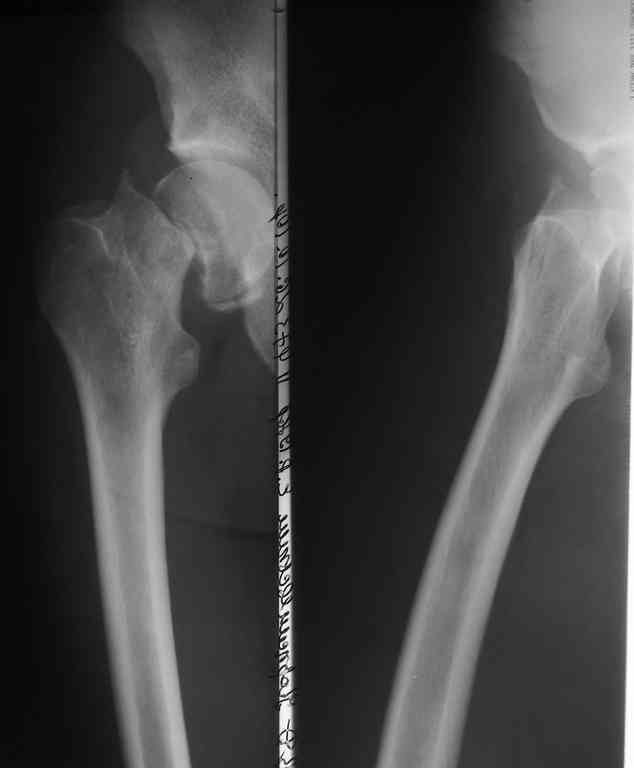

Рентгенография

Если решитесь делать остеосинтез, покажите результат обязательно. Все-таки субкапитальный перелом с вероятным переходом на головку, почти через 3 месяца после травмы. Возможность закрытой репозиции через такой срок вызывает сомнения. Открытая еще больше нарушит кровоснабжение. КТ до операции было бы неплохо сделать.

И прежде провести КТ для оценки пертрохантерной области,где на мой взгляд присутствует трещина, которая может причинить проблемы во время операции.

Вы действительно считаете возможным закрытую репозицию субкапительного garden 4 перелома через 3 месяца после травмы? Если "да" - на каком основании? имеется собственный опыт удачных репозиций или данные литературы? если литературы - какой?

Независимо от метода фиксации, любой перелом шейки бедра может осложниться ложным суставом. Часто у молодых, после травмы с высокой энергией и особенно с вертикальными переломами. Более половина леченных после переломов по Pauwels III заканчиваются аваскулярным некрозом или ложными суставами.

Молодой возраст больного является противопоказанием к артропластике, и необходимо сделать все возможное, чтобы уйти от "внутренней ампутации" головки. С момента травмы более трех месяцев, и жизнеспособность головки пока не вызывает опасений. Свободная подвиженность по линии перелома доказывает, что патология в стадии ложного сустава.

Ипсилатеральный перелом имеет другой режим нагрузки и для решения вопроса необходимо иметь и другие снимки.